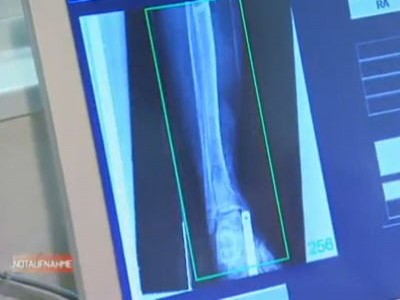

Auf dem Dach des Linzer AKH landet ein Hubschrauber mit einem schwer verletzten Mann, auf den ein großer Baukran gefallen ist. Der Verletzte wurde von den Erstversorgern in künstliches Koma versetzt, damit er den Transport übersteht. Schnellstens bringt ihn ein Assistenzarzt in den Schockraum. Dort wartet der Leiter der Linzer Unfallchirurgie, Prof. Kwasny, auf den Patienten. Die Untersuchung zeigt: Der Patient hat viele offene Wunden, gebrochene Beine und einen enormen Blutverlust. Sofort setzt Prof. Kwasny eine Notoperation an, bei der drei Chirurgen mitwirken, dem Mann das Leben zu retten. Mitten in der OP steht Prof. Kwasny vor der Entscheidung, ob er dem Opfer ein Bein abnehmen muss. Marion, eine Mutter von zwei kleinen Kindern, steht mitten im Umzugs- und Einrichtungsstress. Beim Einkaufen lässt sie plötzlich ihr rechtes Bein im Stich, sie landet im LKH Salzburg mit einer gebrochenen Kniescheibe. Ihre größte Sorge gilt der Frage, wie ihr Mann mit den Kindern allein zurechtkommen wird. Und die junge Turnusärztin Dr. Cornelia Brunner muss den ungeliebten Wochenend-Nachtdienst im AKH Linz schieben. Wenig überraschend bekommt sie es mit einem betrunkenen Jungendlichen zu tun, der sich partout nicht behandeln lassen will.